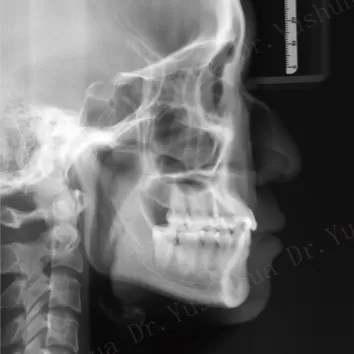

Rayons X avant le traitement

[Radiographie panoramique/Céphalogramme latéral]